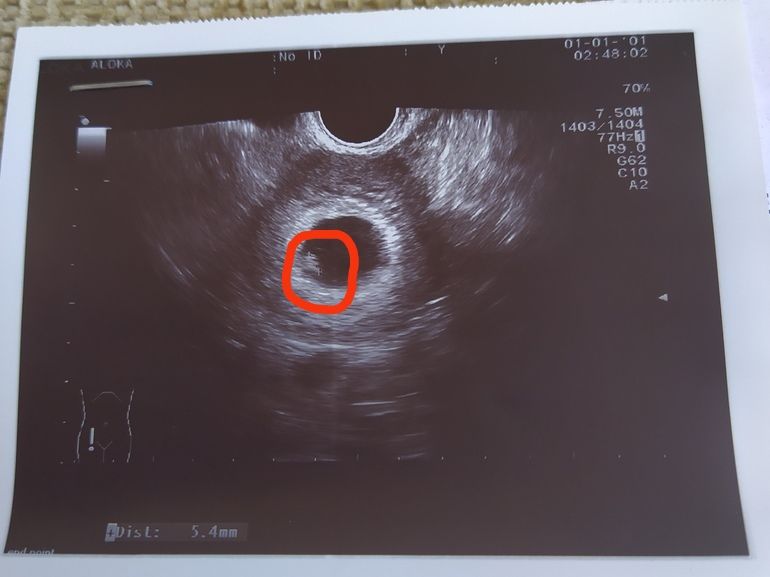

Настя , а размеры какие жм и эмбриона? У меня вот тоже на фото не видно жм,а эмбрион с жм практически одинаковые по описанию ктр 5,4,а жм 4,9 Изображение

Настя , странно,9,2 жм? Это огромный,такой жм без эмбриона это уже 100% замершая,но на фото это точно не жм,он не так выглядит,она наверное с ктр перепутала,это ктр 9,2,а не жм,но странно чего тогда сб нет? Очень странное УЗИ, какой-то не профессионал его делал, переделайте в другом месте,и заключение ранний срок,но пя 21 какой это ранний срок

Настя , но в описании нет ничего про эмбриона,она должна была указать размеры эмбриона и сб,а она жм 9,2 написала,она видимо перепутала,да нет на фото жм вообще,нормальных размеров он,был бы 9,2 это был бы огромный и выглядит он как кружок,а на фото нет его

Настя , срок наверное еще маленький очень, поэтому он больше эмбриона))) сердце уже стучит?у меня просто на сроке 6,4 и был такой жм,а эмбрион она показала рядом просто точечка, сказала вот тут он зарождается.сердцебиения еще не было больше я не ходила, только в 12 недель.поэтому могу, конечно ошибаться

elena, сегодня ровно 6 недель) говорит трепещет, но сердцебиение еще не посчитать Как то так ))